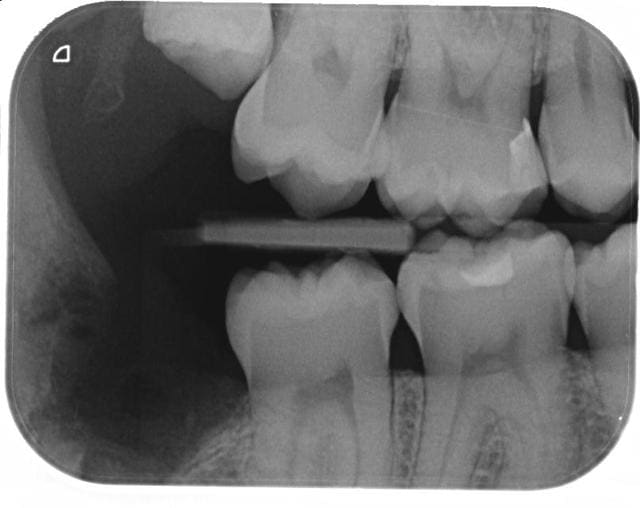

J ai du mal avec cette image. Un bon pano et 2 retro alveolaires ca me parle bien mieux...vieille ecole sans doute

Informer du risque de lesion, torsion du V3 :0)

De toute facon, cela arrive dans 3% des dds. Ensuite savoir que les problemes de sensibilite sont reversibles a 90% dans les 2 ans...

exemple Exo 48 avec sensibilite post op. a 1 mois. A 6 mois la patiente vient faire un etat des lieux avec un neurologue si persistance d absence de sensibilite.